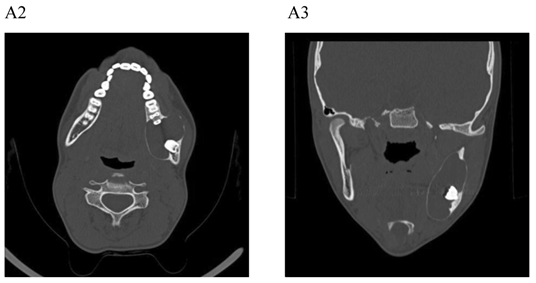

For most of the cysts, plain film radiography (PFR) was an adequate imaging modality. In some of the cases, CT with MPR program was also performed. The CT with MPR software, originally designed for implant dentistry, has proven to be useful in the evaluation of jaw abnormality and pathology [4, 15-19]. Using this software program, anatomic structures, such as the mandibular canal, mental foramen, incisive canal, and maxillary sinus, can be seen in cross-section. CT with MPR has also been shown to be superior to PFR in demonstrating cystic lesions of the jaws and in evaluating bone regeneration following marsupialization of jaw cysts [17-19].

The main advantage of CT with MPR is that it allows planning of the surgical approach with the least morbidity to the adjacent anatomic structures [20]. Despite the advantages, CT should not be used routinely, but rather reserved for large lesions, particularly those where extension into the nasal cavity, maxillary antrum, orbit, or pterygomaxillary space must be assessed.

The treatment objective is restoring the morphology and function of the affected area. There are two basic surgical procedures, namely marsupialization (decompression) (Fig.1) and enucleation. Marsupialization, a relatively simple procedure, consists of surgically producing a “window” in the cystic wall to relieve intra-cystic tension. After this, the cystic cavity slowly decreases in size. The cavity is lightly packed with paraffin gauze until the line of junction between the cystic lining and the oral mucosa has healed. Three to six months later, enucleation is performed [16].

Figure 1

Dentigerous cyst affecting the left mandible of a 15-year-old boy treated by marsupiallization. At presentation, there was an acute infection in the area. A) Pre-operative radiographs: 1) Panoramic radiograph demonstrating a tooth within a large radiolucent area in the left mandible; 2) Axial CT scan demonstrating expansion of the body of the left mandible with very thin buccal and lingual cortices. A tooth is within the lumen; 3) Coronal CT of the mandible demonstrates an expansion of the ascending ramus of the left mandible with very thin cortical borders. A tooth is within the lumen. B. Postoperative radiographs: 1) Panoramic radiograph shortly post-marsupialization, extraction of tooth 37 that was adjacent the cyst as well as tooth 38 that was within the cyst; 2) Panoramic radiograph one year post-treatment. The radiodensity of the cystic area is similar to normal bone, indicating complete bone regeneration.

Enucleation with primary closure is the treatment of choice [22]. It is a one-stage surgical treatment followed by periodic radiographic examinations at regular intervals to observe the progress of bone regeneration of the defect. It also allows pathologic examination of the entire specimen for histopathologic diagnosis. Enucleation can be done only when the jaw bone adjacent to the cyst is intact. If CT demonstrates erosions in the buccal or lingual cortices, marsupialization should be the treatment of choice (Fig. 1) [4].